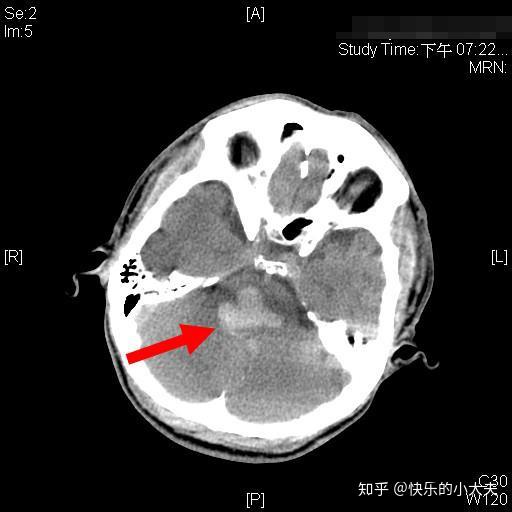

脑干出血(脑桥背侧)

头ct可见桥脑占位合并出血